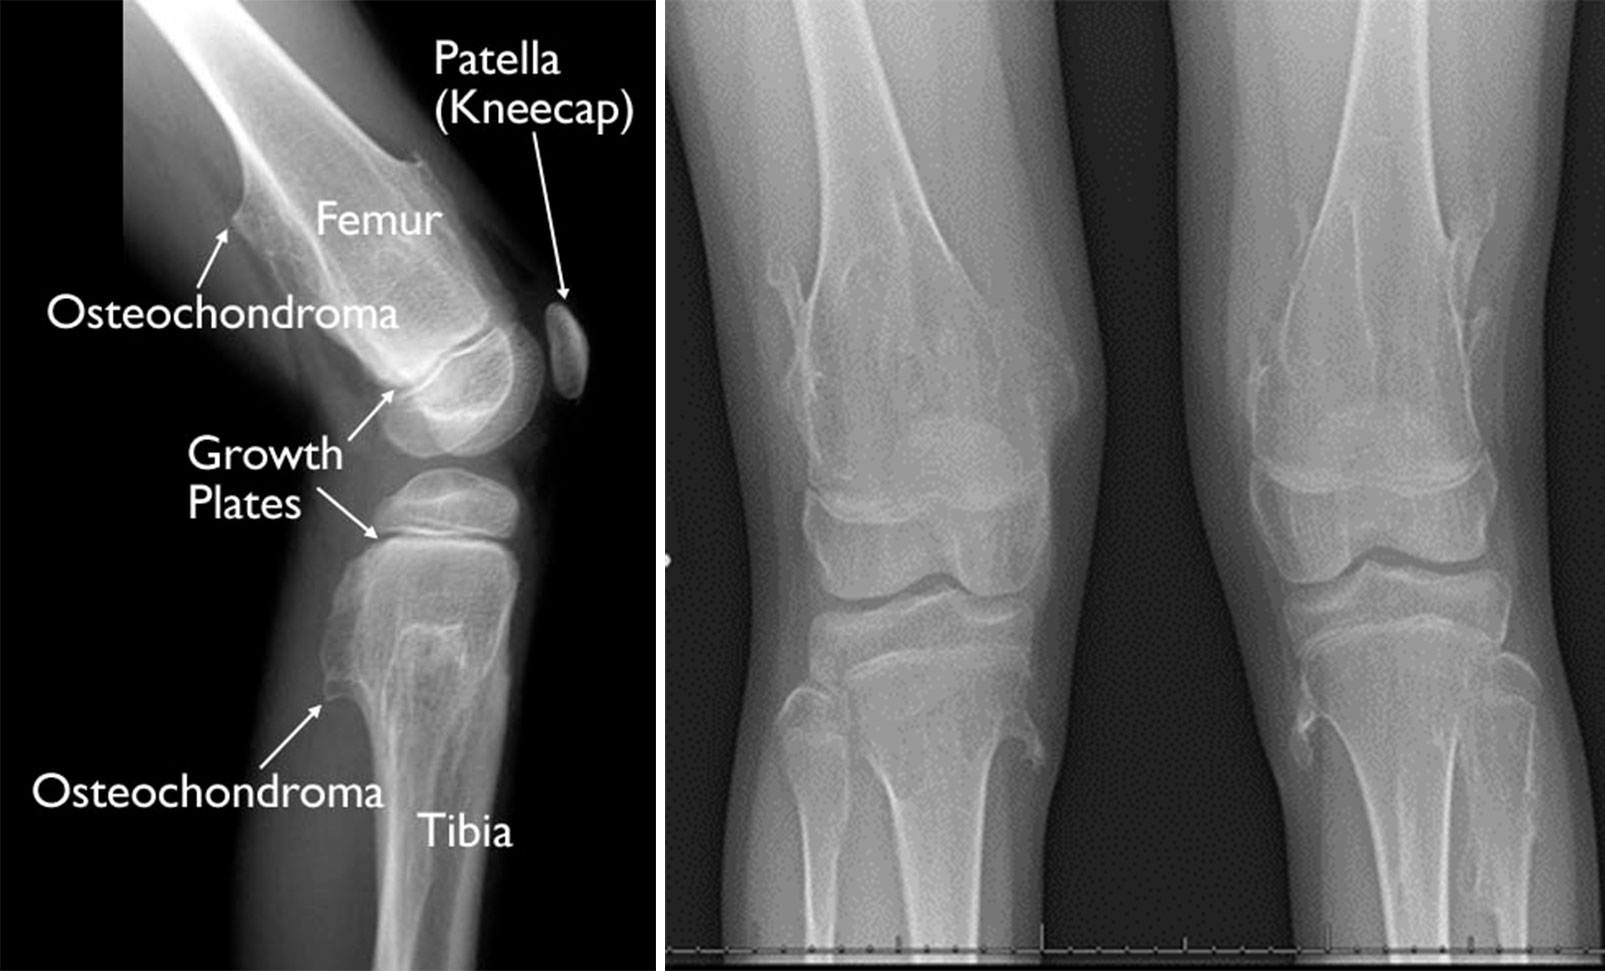

Multiple osteochondromas

Tumors in the femur and tibia are apparent in these X-ray of a child's knee.

The number and location of the osteochondromas vary. Both pedunculated and sessile tumors may develop. In more severe cases, MHE can cause bones to grow abnormally. For example, many patients have: